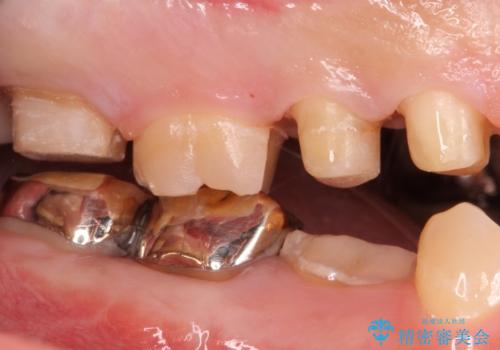

奥歯は十分な歯の高さがなかったため、クラウンをかぶせる前に歯周外科治療で歯の高さを出しています。

歯科に通うようになってから磨き残しの状態も改善されていきました。